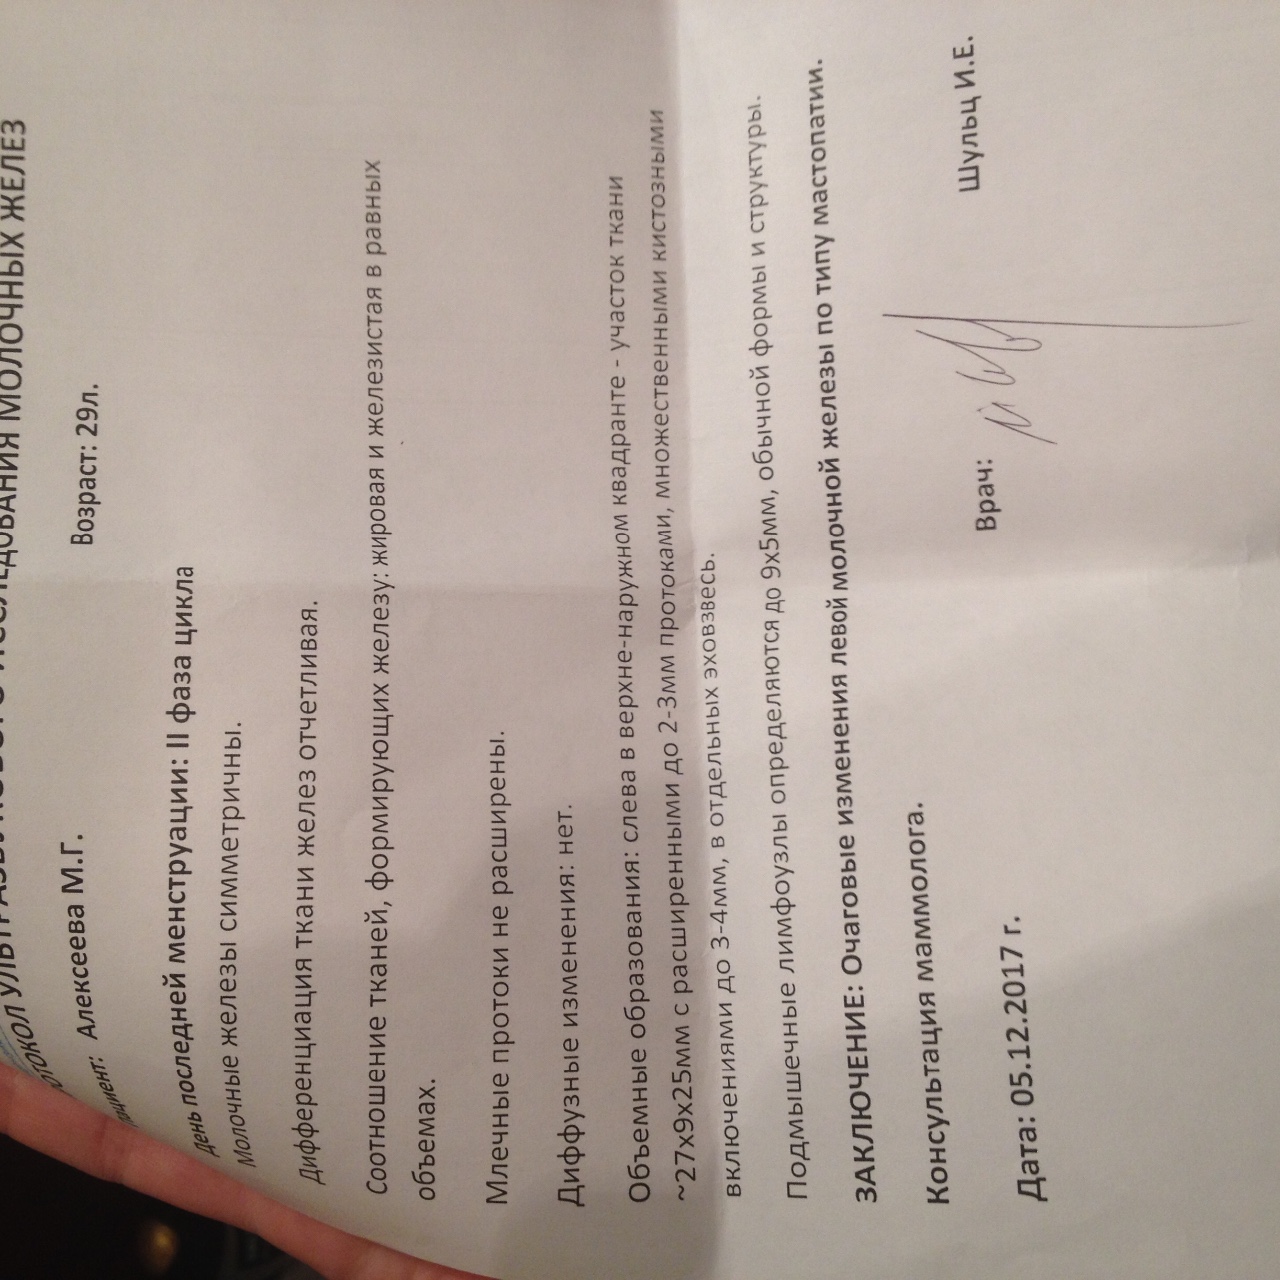

Фиброзно-кистозная мастопатия на УЗИ